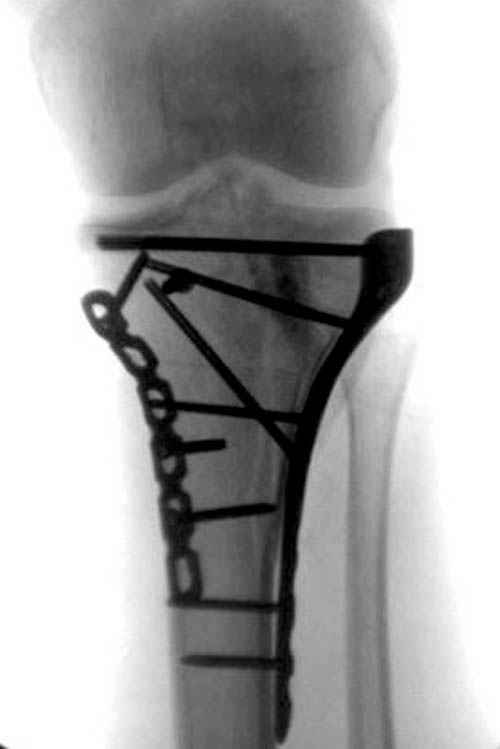

[Ortho] перелом мыщелка и диафиза большеберцовой кости - тактика?

Надеюсь, представленные снимки разных случаев помогут разобраться в тактике, и критика примется без личной обиды.

Вложение не в текстовом формате было извлечено…

Имя     : 13 Med plateau fx.JPG

Тип     : image/jpeg